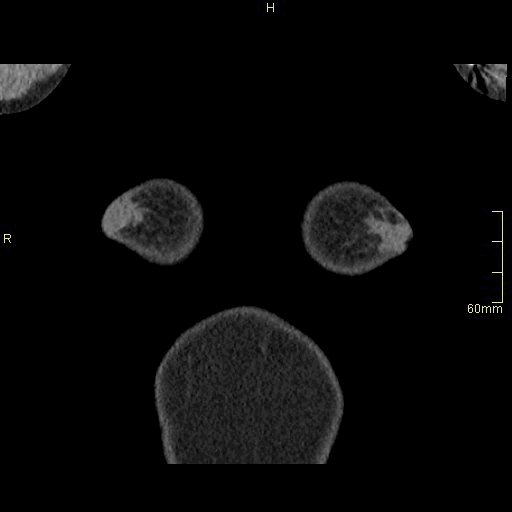

Lung (Axial)

Lung (Coronal)